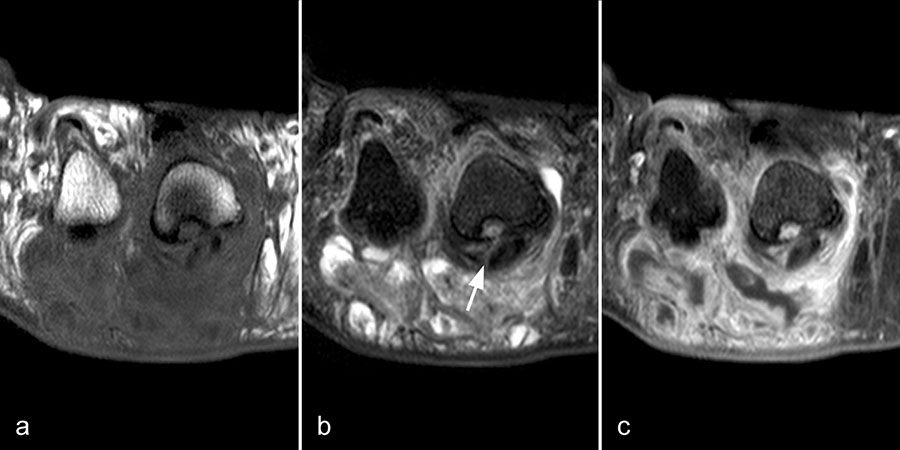

Der Begriff Morton-„Neurom“ ist im Grunde veraltet und irreführend, denn es handelt sich weder um einen Nerven- noch um einen Nervenscheidentumor, sondern um eine perineurale Fibrosierung. Da das interdigitale Gefäßnervenbündel charakteristisch in die Läsion hinein- und distal auch wieder aus der Läsion herauszieht, entsteht lediglich das Bild eines vom Nerven ausgehenden Tumors. Die charakteristischen Merkmale von Morton-„Neuromen“ sind deren Lage plantar auf Höhe der Metatarsaleköpfchen und die oft typische tropfenförmige Konfiguration (Abb. 10).

Aufgrund des hohen Bindegewebsanteils sind sie in der MRT in T2-gewichteten Bildern in der Regel auffallend signalarm, die T1 zeigt eine unspezifische Weichteilintensität. Die Anreicherung nach intravenöser Kontrastmittelgabe ist sehr variabel und erlaubt somit kaum diagnostische Rückschlüsse.

Durch seitliche Kompression des Fußes verlagern sich Morton-„Neurome“ oft weiter nach plantar in die Weichteile. Klinisch entspricht dies dem sogenannten Mulder-Zeichen 4. In der Bildgebung kann man sich den Effekt zu Nutzen machen, indem man in Bauchlage untersucht und durch die seitliche Fixierung eine entsprechende Kompression erzeugt. Die Befunde sind dann oft deutlich besser zu erkennen (Abb. 11).